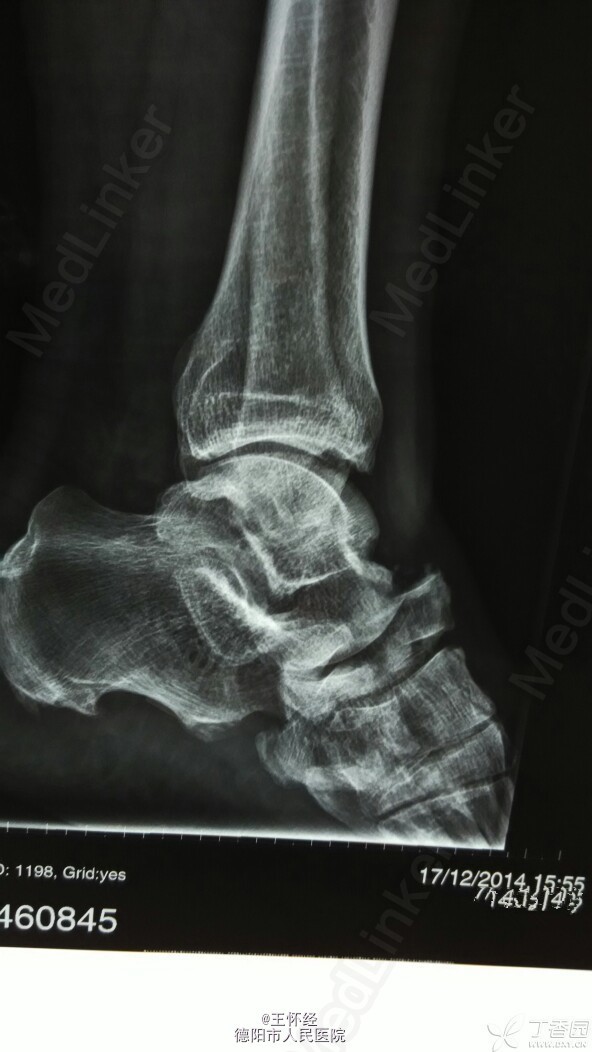

舟骨骨折

患者男性,49岁,外伤后急诊入院,发现舟骨骨骨折,行手术治疗